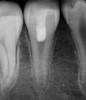

(3.) Preoperative radiograph of necrotic permanent tooth No. 29.

Figure 3

(4.) Immediate postoperative radiograph after second visit for regenerative endodontic treatment on tooth No. 29.

Figure 4